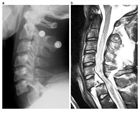

1. 高エネルギー外傷による脊椎損傷が疑われる場合には、呼吸状態、循環動態などの全身状態評価と必要な救急救命処置を優先し、その後に神経学的評価・画像評価を行うことが推奨される。

1. 頭蓋頚椎、頚胸椎、胸腰椎の各移行部での脊椎損傷は他の臓器との重なりが多く、単純X線では見落とされることがあり、CTによる評価が推奨される。

1. 高齢化に伴い強直性脊柱や骨粗鬆症を基盤とした脊椎損傷の比率が上昇しており、その病態、損傷形態に応じた治療法、手術法が求められる[1]